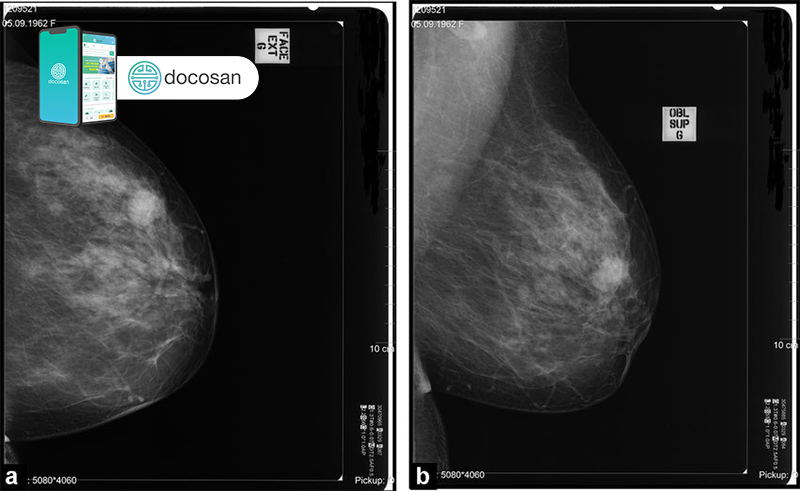

- Chụp nhũ ảnh tầm soát được thực hiện như một bước thăm khám thường quy nhằm phát hiện sớm bệnh ung thư hoặc những thay đổi bất thường ở vú. Việc chụp nhũ ảnh tầm soát chỉ chụp 1 phim tư thế chếch.

- Chụp nhũ ảnh chẩn đoán yêu cầu chụp từ nhiều vị trí khác nhau hơn so với chụp nhũ ảnh tuyến vú sàng lọc. Bác sĩ chụp X quang cũng có thể cần phóng đại một số khu vực có dấu hiệu đáng nghi ngờ.

Sau đó bạn đứng trước một chiếc máy X-quang và đặt một phần ngực lên một bàn chụp. Bác sĩ hoặc kỹ thuật viên có thể sử dụng một băng dính ghi dấu X-quang nhỏ dán lên phần vú – nơi nghi ngờ có khối u. Bác sĩ chỉnh hướng tấm plastic phẳng đặt đè ép vú theo hướng tuỳ mục đích chụp nhũ ảnh. Tấm plastic sẽ ép chặt ngực để ghi nhận hình ảnh của mô vú.

Hình ảnh từ chụp X-quang tuyến vú có thể giúp phát hiện các mảng vôi hóa, cặn canxi trong vú hoặc những tổn thương bên trong nhu mô vú (có thể lành tính hoặc ác tính) và các hạch di căn nếu có. Mặt khác, việc so sánh nhũ ảnh vừa mới chụp với các nhũ ảnh trước đó cũng hỗ trợ bác sĩ trong việc theo dõi tiến triển của một tổn thương trong khu vực khảo sát.